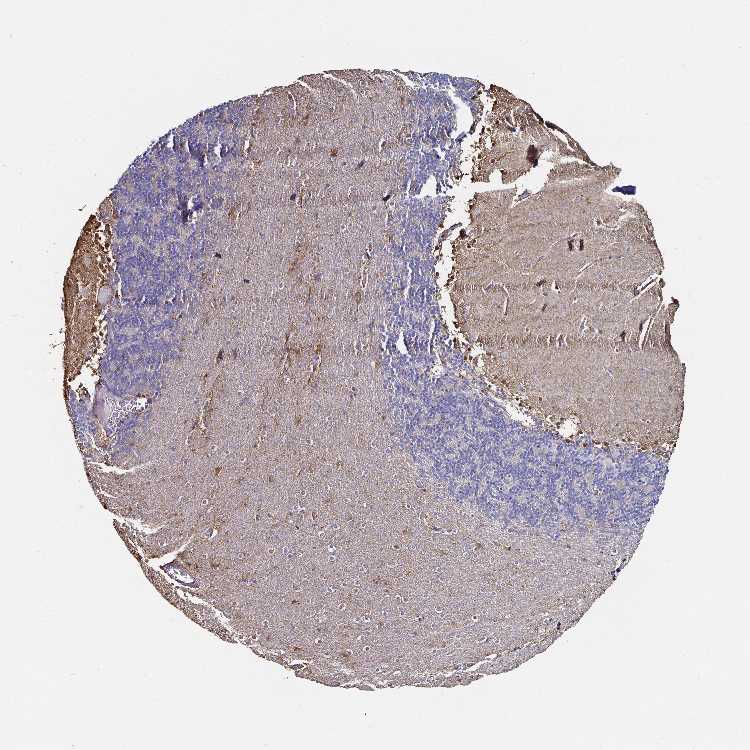

CEREBELLUM - Antibody stainingi

Antibody staining in the annotated cell types in the current human tissue is reported as not detected, low, medium, or high, based on conventional immunohistochemistry profiling in selected tissues. This score is based on the combination of the staining intensity and fraction of stained cells.

Each image is clickable and will lead to virtual microscopy that enables deeper exploration of all samples and also displays staining intensity scores, fraction scores and subcellular localization as well as patient and tissue information for each sample.

Antibody HPA017369Antibody CAB000023Antibody CAB040544Antibody CAB055506Antibody CAB058688

GLUC cells - cytoplasm/membrane -High---

Processes in granular layer -Medium---

Processes in white matter -Medium---